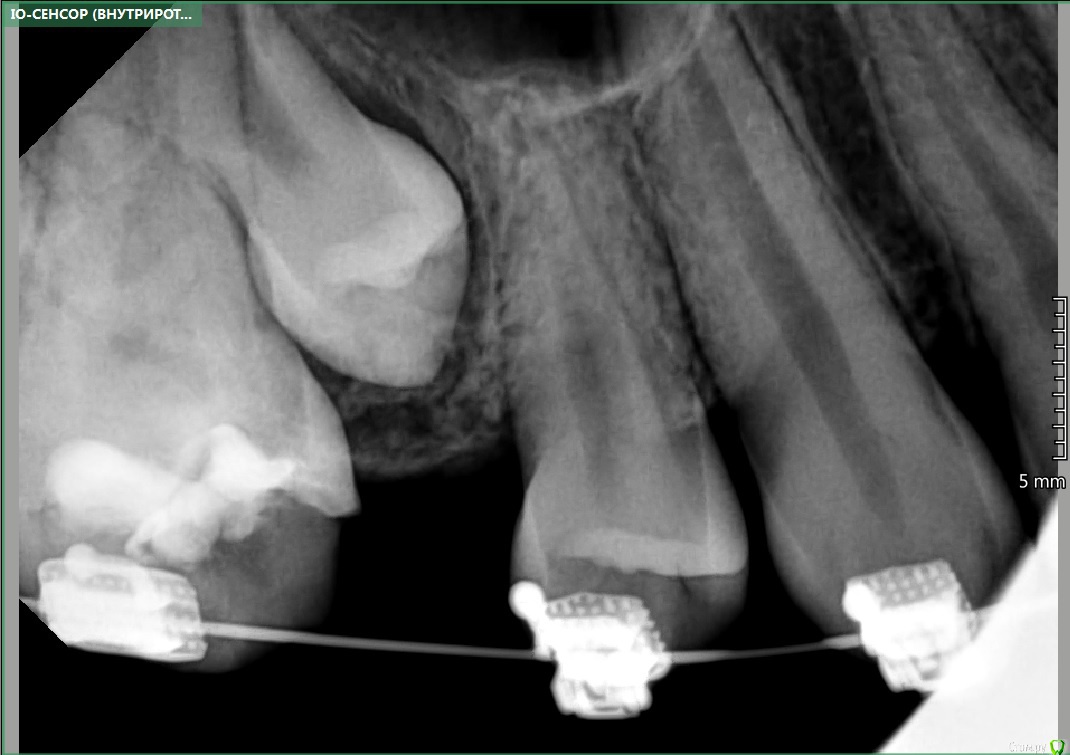

Garrus Опубликовано 1 февраля, 2018 Поделиться Опубликовано 1 февраля, 2018 Пациент 14 лет,ортодонт направил раскрыть 2.5 зуб.Подскажите,каков на ваш взгляд прогноз у зуба? Какой доступ предпочтительнее?Между орто и прицельным ~5 мес Ссылка на комментарий

Brigita Опубликовано 1 февраля, 2018 Поделиться Опубликовано 1 февраля, 2018 По снимку не понятно, где он лежит, но похоже вестибулярно? Если так, открывайте вестибулярно , делайте хороший доступ - побольше, и выпиливайте кость, не жалейте. и не слушайте хирургов, которые скажут делать отверстие по диаметру кнопки .Доступ должен быть таким, чтобы приклеить ее как можно выше, тогда движение пойдет. Ссылка на комментарий

red_butler Опубликовано 2 февраля, 2018 Поделиться Опубликовано 2 февраля, 2018 Нужно щупать или делать Кт Ссылка на комментарий

Kazankov.Egor Опубликовано 2 февраля, 2018 Поделиться Опубликовано 2 февраля, 2018 По снимку не понятно, где он лежит, но похоже вестибулярно? Если так, открывайте вестибулярно , делайте хороший доступ - побольше, и выпиливайте кость, не жалейте. и не слушайте хирургов, которые скажут делать отверстие по диаметру кнопки .Доступ должен быть таким, чтобы приклеить ее как можно выше, тогда движение пойдет.что на счёт стадии формирования и тракции? Ссылка на комментарий